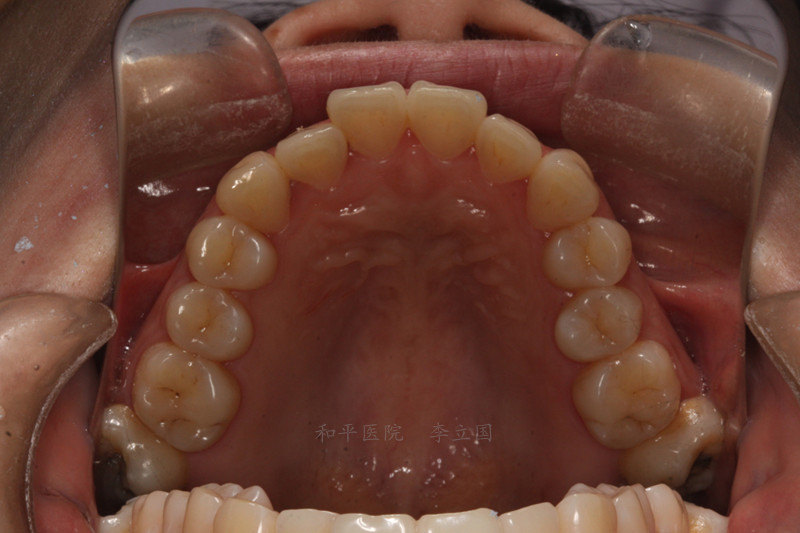

上双侧7锁合矫正设计思路

隐适美真人方案地包天后牙锁合

什么是锁合锁合如何解除

锁牙合图片